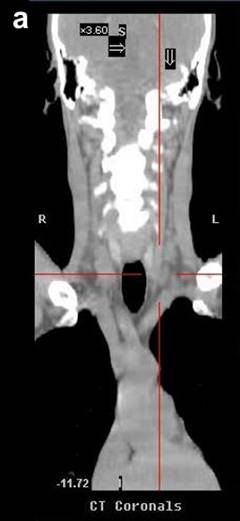

A 51-year-old Caucasian male presented with a history of progressive jaundice, loss of weight, acholic stools, and bilirubinuria. He was found to have a pancreatic head mass on a transabdominal ultrasound and CT scan of the abdomen. Fine needle aspiration cytology (FNAC) of the pancreatic mass confirmed well-differentiated ductal adenocarcinoma. The patient had unresectable disease given that the tumor encased approximately 180 degrees of the superior mesenteric artery. The initial CT scan of the abdomen showed nodules in the liver that were suspicious but not confirmatory for metastasis. Therefore, PET/CT scan was performed where no liver metastases were noted. CT scan of the neck did not demonstrate any evidence of supraclavicular metastasis (Figure 1). However, there was uptake of 18-fluorodeoxyglucose (FDG) with a standard uptake value (SUV) of 4.3-4.7 in the medial left supraclavicular region that was suspicious for nodal metastasis (Figures 2 and 3). FNAC of the left supraclavicular lymph node showed poorly differentiated metastatic adenocarcinoma consistent with a pancreatic primary. Therefore, the final clinical staging was stage IV (T4NXM1, Table 1).

Figure 1. CT scans of Patient #1 before (a.) and after (b.) chemotherapy. CT scans do not demonstrate presence of supraclavicular metastasis in Patient #1. |

In all of the three cases reported in this article, PET/CT scans detected supraclavicular lymph node involvement that was not identified by the standard imaging protocol, CT scan of the chest and abdomen, for pancreatic cancer. Of note, CT scans, which are the de facto surveillance imaging modality, failed to detect metastasis in all three cases (Figure 1). Of course, this was predominantly due to the fact that CT scans of the neck would not be part of a routine surveillance algorithm for patients with pancreatic cancer.